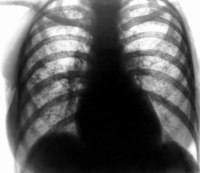

• Рентгенографии и КТ грудной клетки. Выявляется деформированный сетчатый лёгочный рисунок. На его фоне с двух сторон визуализируются пятнистые затенения, расположенные в нижних и средних отделах лёгких. Тени могут сливаться и образовывать округлые или линейные конгломераты. Субплеврально определяются эмфизематозные буллы. В базальных лёгочных отделах встречаются бронхоэктазы.